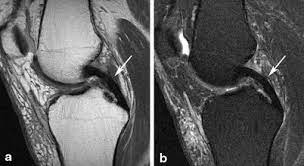

WHAT ARE MCL, LCL, PCL, AND COMPLEX LIGAMENT INJURIES?

- MCL (Medial Collateral Ligament): The MCL is located on the inner side of the knee and provides stability against forces that push the knee inward. MCL injuries are often caused by direct blows to the outside of the knee.

- LCL (Lateral Collateral Ligament): The LCL is located on the outer side of the knee and provides stability against forces that push the knee outward. LCL injuries are less common and often occur due to direct trauma or hyperextension.

- PCL (Posterior Cruciate Ligament): The PCL is located at the back of the knee and prevents the shinbone from moving backward relative to the thighbone. PCL injuries are often caused by high-impact trauma, such as car accidents or falls.